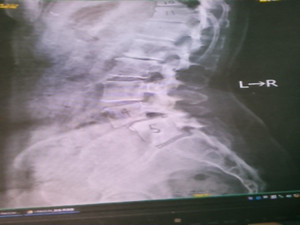

尻もち尾骨骨折4日前

東京都の40代の女性、4日前に尻もちをついて尾骨を骨折。

日常的に痛く座れないため会社を休んでいる状態。

尾骨整復術で痛みは軽減。あと4回の施術で治癒。